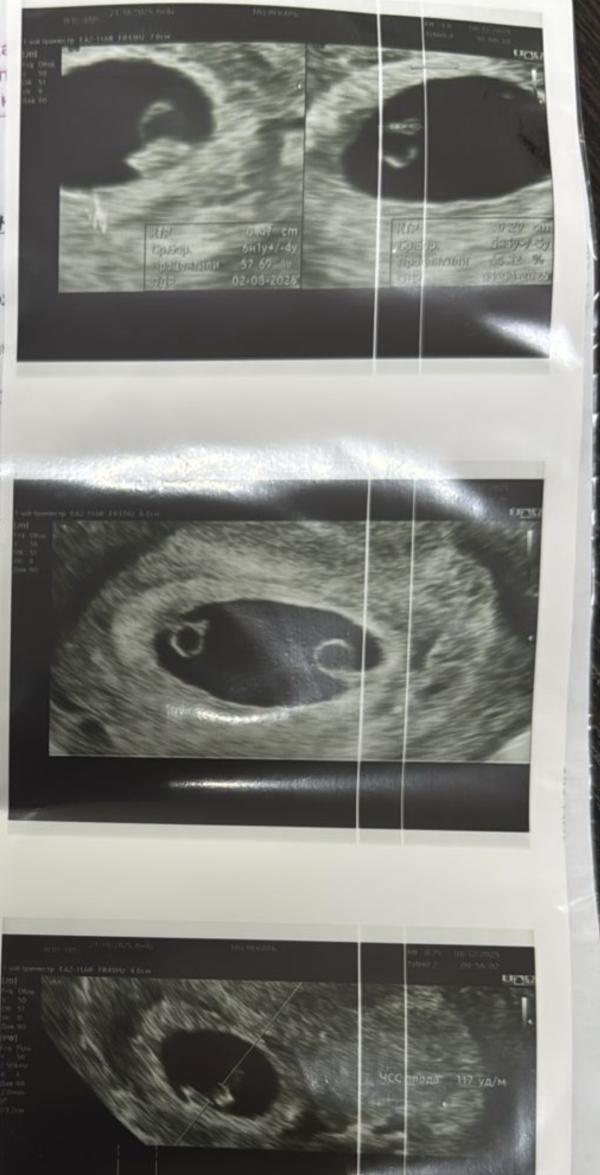

Монохориальная моноамниотическая двойня на 5-6 неделе: что дальше?

Монохориальная,моноамниотическая двойня сроком 5-6 недель

У одного сердечко бьется а у другого через 7-10 дней проверим 🙌🏻